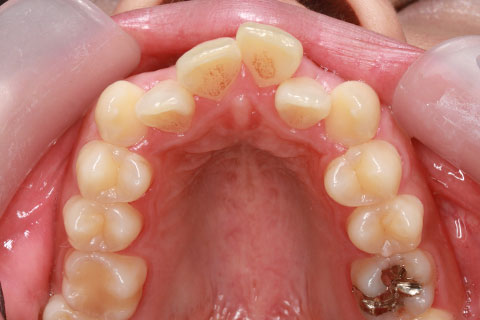

前歯のみの部分的舌側矯正1(矯正期間10ヶ月)

- 年齢・性別

- 21歳女性

- 治療期間

- 10ヶ月

- 抜歯

- 左上2番

- 治療費

- 50万円(税込み)

- 治療内容

- 前歯一本抜歯して凸凹を改善した。

- 施術の副作用(リスク)

- 装置が裏側について、目視ができないため、しっかりとブラッシングができているかどうかわかりにくい。